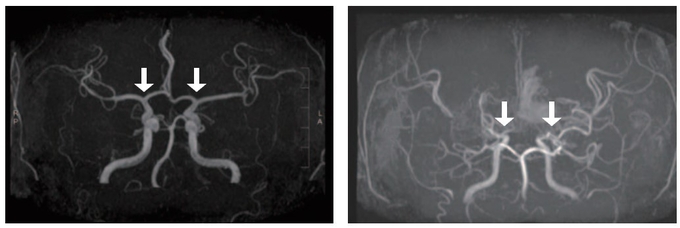

소아 모야모야병은 뇌로 혈액을 공급하는 혈관이 특별한 원인 없이 점차 좁아지는 만성 진행성 뇌혈관질환이다. 이 질환이 있으면 부족한 혈류를 보충하기 위해 비정상적인 미세혈관이 형성되는데, 이들은 혈류를 충분히 공급하기 어렵고 파열되기 쉬워 뇌경색·뇌출혈 등 소아 뇌졸중을 유발할 수 있다.

모야모야병 확진은 뇌혈관 조영술을 통해 이뤄진다. 그러나 검사 전 진정이나 마취를 필요로 하는 경우가 많아 소아 환자의 부담이 커 새로운 진단 방법이 필요했다. 최근 뇌척수액이 중추신경계 질환 바이오마커를 발굴하는 유용한 자원으로 주목받고 있으나, 이를 활용한 대규모 모야모야병 연구는 부족한 실정이었다.